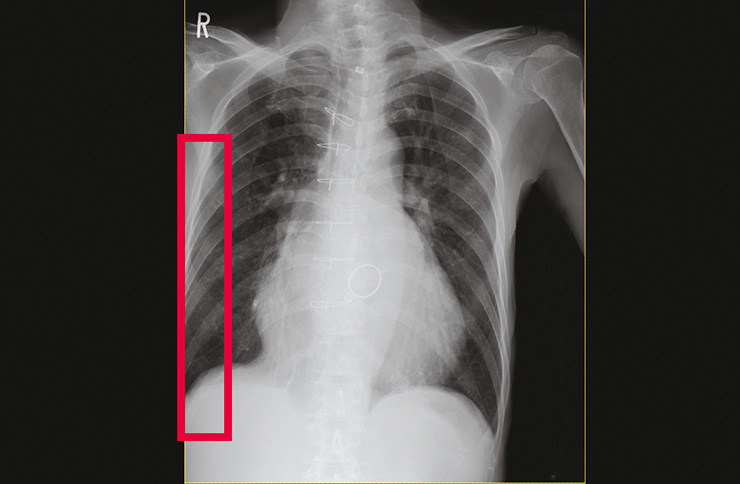

Images with lung field deficiency

The CS-7 is equipped with a function that automatically detects potentially rejected images such as those with “lung field image deficiency” or “body movement” using image analysis immediately after shooting.